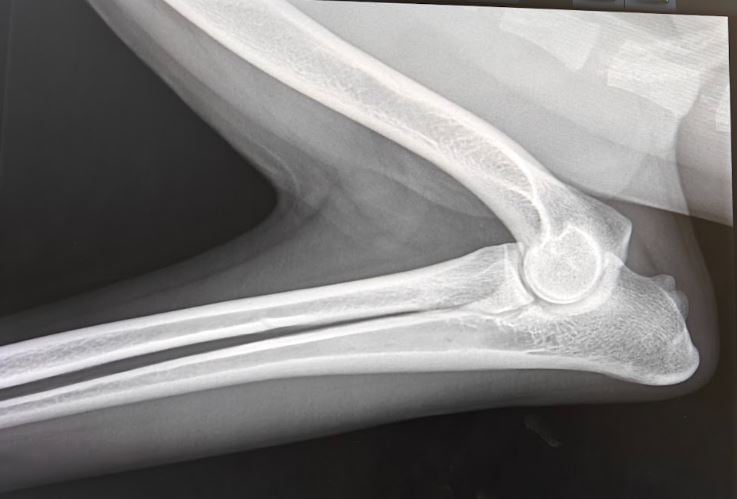

AD – Albueledsdysplasi

AD er en samlet betegnelse for forskellige lidelser i albueleddet.

Men ligesom med HD, så giver lidelsen anledning til forandringer i albueledet. AD er ligeledes polygenetisk nedarvet, hvor både gener og miljøpåvirkning har betydning for om hunden er disponeret for at udvikle lidelsen.

AD bedømmes også ud fra røntgenbilleder, hvor hunden får tildelt en status fra 0 til 3. Hunde med status 0 betragtes som frie, 1 er en let grad, 2 er moderat og 3 er svær grad, og bør på ingen måde anvendes i avl.

Forekomsten af AD hos Collies er sjælden.

I Finland blev der i årrækken 2002 til 2022 AD-fotograferet 4133 Collies,

hvor blot 4% fik en anmærkning, og 96% af Collierne blev betragtet som frie!

I Danmark bliver der AD fotograferet langt færre Collies,

og kendskabet til AD i den danske collie bestand er ikke lige så oplyst.